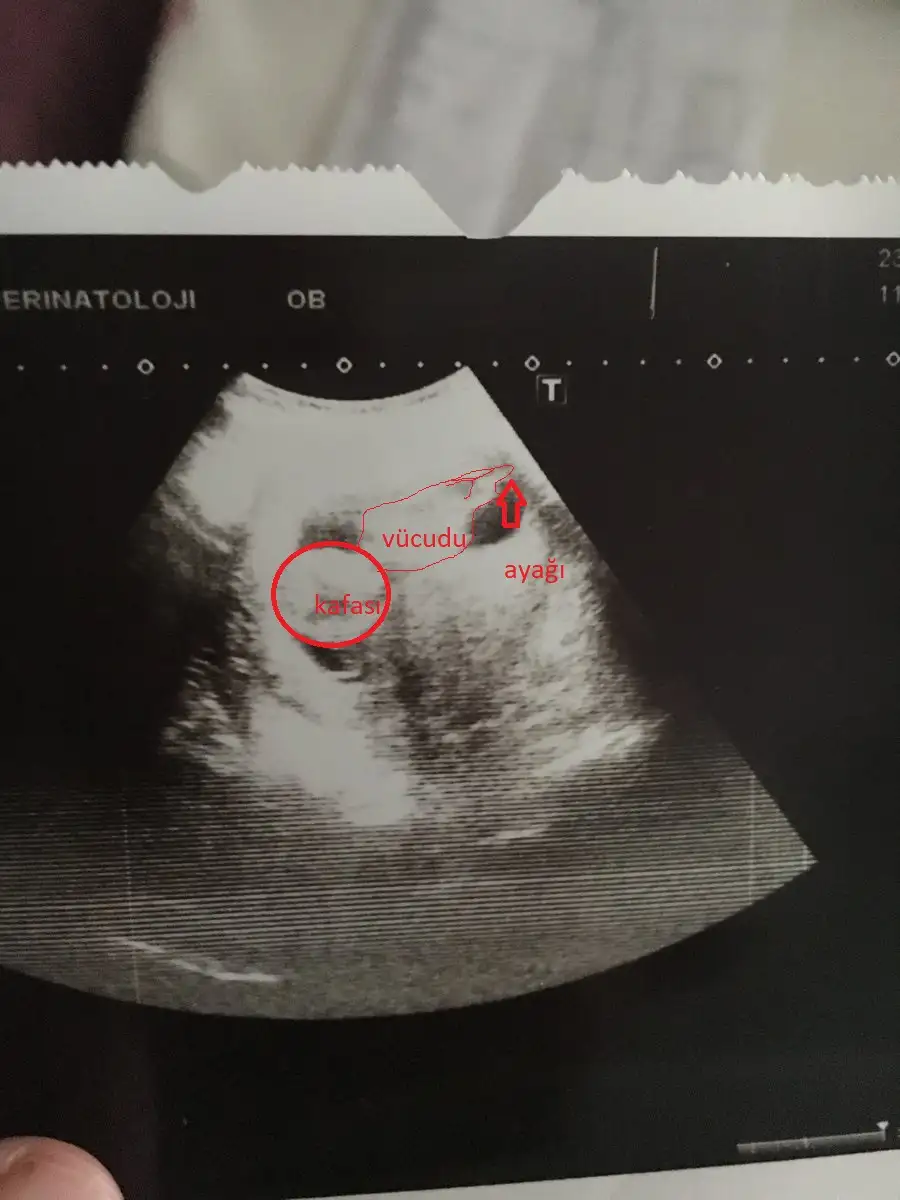

Resim yükledim kızlar ama ben bu usg Fotoğraflarından hiç bişi anlamıyorum başını poposunu bile ayıramıyorum ki nerde cinsiyet tahmini anlayanlardan yorum bekliyorum

Bana 100 de 100 erkek dedi ama simdi sonradan degismis birinin falan yazinca bi emin olamadim. Baktim baktim su asagida ki pipicik olamaz dimiteyzeleri bi bakin sizde.